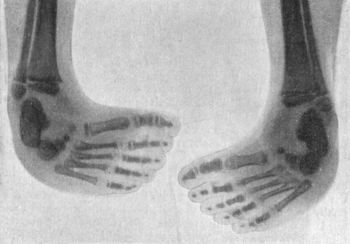

142.Bilateral Congenital Club-foot in an Infant274

143.Radiogram of Bilateral Congenital Club-foot in an Infant275